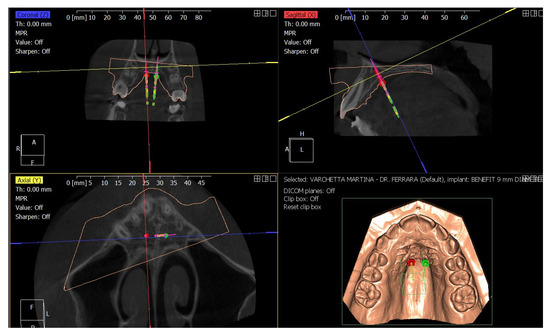

4.3. Treatment Strategy

4.4. Treatment Progress